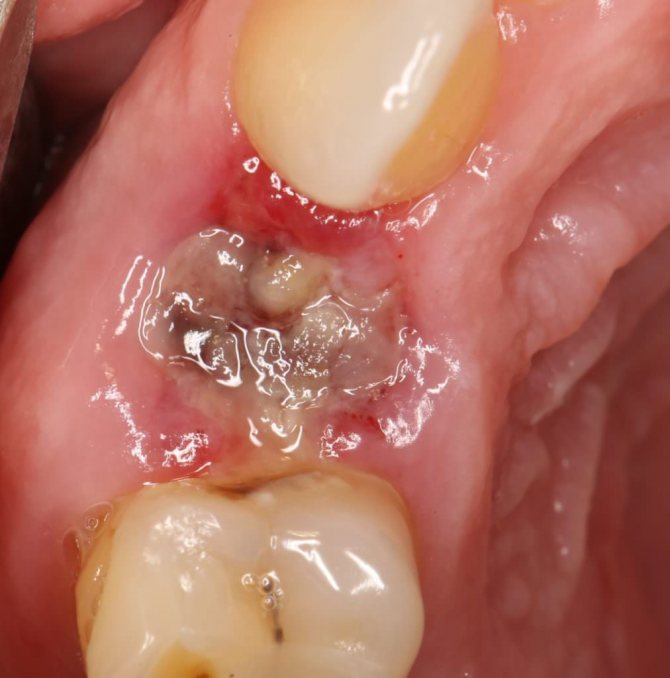

В норме в лунке должен образоваться кровяной сгусток.

После экстракции корня обязательным правилом является тщательная обработка альвеолы. В этих целях лунка промывается специальными антисептиками, с последующим прикладыванием к ранке специальных противовоспалительных средств.

Они используются не только в терапевтических целях, но и в профилактических несмотря на наличие воспалительного процесса в лунке.

Их применение способствует более быстрому заживлению ранки и не допускает развития воспалений.

Снятие воспаления

При удалении гнилого корня довольно часто обнаруживается воспалительный процесс. Чтобы ранка благополучно заросла и не загноилась, принято делать обработку антисептиком. Но одна обработка не обеспечит должной профилактики, поэтому в свежую лунку закладывают противовоспалительный препарат. С ним лунка заживет быстрее, а у пациента будет меньше шансов заболеть альвеолитом.